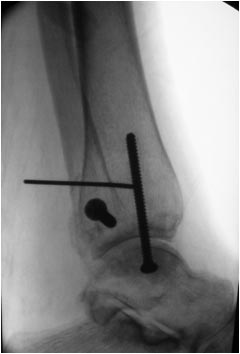

Оперировал эту пациентку 23 лет 11 лет назад через 8 месяцев после

похожего на представленный Вами остеосинтез. На первой операции перелом

малоберцовой кости в нижней трети был просто не замечен. За счет

восстановления оси быстро развившийся артроз протекал благоприятно. В

результате артродез был выполнен только в прошлом году, через 10 лет

после второй операции. И боли беспокоили пациентку только в течение года

перед артродезом.